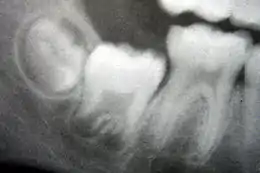

A: émail

B: dentine

Les cellules superficielles de la papille dentaire augmentent brusquement de taille et se différencient en odontoblastes qui vont former la dentine[8]. Les chercheurs croient que l'apparition des odontoblastes ne se ferait pas s'il n'y avait pas eu les changements intervenus dans l'épithélium adamantin interne. En même temps que les cellules de l'épithélium adamantin interne se modifient et que se forment les odontoblastes à partir de la pointe des cuspides, les odontoblastes se mettent à sécréter une substance, une matrice organique, la prédentine, dans leur environnement immédiat. Cette matrice organique contient le matériel nécessaire pour la formation de la dentine. En formant la matrice organique, les odontoblastes reculent et migrent vers le centre de la papille dentaire. Ainsi, contrairement à l'émail, la dentine se forme de l'extérieur vers l'intérieur de la dent. Les odontoblastes, en se déplaçant vers l'intérieur de la papille, laissent des filaments cytoplasmiques dans la matrice, les fibres de Tomes qui en disparaissant laisseront place à de fins canaux, les canalicules de la dentine ou canalicules de Tomes. L'aspect tubulaire de la dentine que l'on observe au microscope est le résultat de la formation de la dentine autour de ces filaments[1].

Après le début de la formation de la dentine, les cellules de l'épithélium adamantin interne sécrètent une matrice organique contre la dentine. Cette matrice se minéralise et devient immédiatement l'émail des dents. En dehors de la dentine, on retrouve les améloblastes, qui sont des cellules qui continuent le processus de formation de l'émail, par conséquent, l'émail se forme de l'intérieur vers l'extérieur par ajout de nouveaux éléments à la surface externe de la dent en développement.